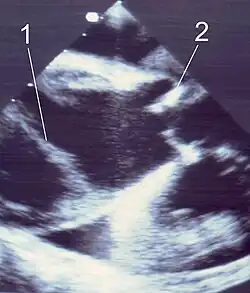

| Transösophageale Echokardiografie (TEE) |

TEE mit Farbdoppler farbig wahres Lumen |

| Querschnitt durch die Aorta ascendens 1 Dissektionsmembran – 2 Aortenklappe | |

Bei der üblichen Ultraschalluntersuchung des Bauchraumes (abdominelle Sonografie) können die im Bauchraum gelegenen Abschnitte der Aorta (Aorta abdominalis) meist dargestellt und mehr oder weniger gut beurteilt werden. Zusätzlich sind im Rahmen der normalen Ultraschalluntersuchung des Herzens (Echokardiografie) oft die ersten zwei bis fünf Zentimeter der Aorta mäßig gut beurteilbar. Insgesamt ist aber die diagnostische Genauigkeit der einfachen Ultraschallverfahren zur Erkennung von Aortenerkrankungen nur mäßig, weil die Darstellungsqualität durch die Brust- und Bauchwand hindurch oft schlecht ist und Teile der Aorta ascendens sowie der Aortenbogen und die im Brustraum gelegenen Abschnitte der Aorta descendens nicht beurteilbar sind (Sensitivität 59–85 %, Spezifität 63–96 %).

Die TEE hingegen erlaubt eine gute Darstellung der herznahen Aortenabschnitte und der Aorta descendens im Brustraum. Aufgrund der hohen räumlichen Auflösung ist eine vorhandene Dissektionsmembran fast immer zu erkennen, mit Hilfe der Dopplertechnik kann darüber hinaus das wahre Lumen zuverlässig vom falschen Lumen abgegrenzt werden. In vielen Fällen sind das entry und ein evtl. vorhandenes re-entry sichtbar. Eine Aortenklappeninsuffizienz kann ebenso exakt diagnostiziert werden wie ein Perikarderguss. Hingegen sind Veränderungen am Aortenbogen, an den dort entspringenden hirnversorgenden Gefäßen und an der Aorta abdominalis in der TEE oft unzureichend dargestellt, diese Regionen werden auch als „blinde Flecken“ der TEE bezeichnet. Die Sensitivität zur Erkennung von Aortenerkrankungen beträgt 88–99 %, die Spezifität 95–98 %.